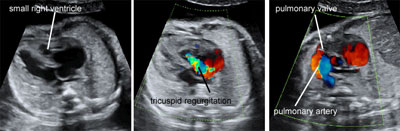

Pulmonary atresia with intact ventricular septum

Legend:Pulmonary atresia with intact ventricular septum: the right ventricle is small, there is significant tricuspid regurgitation, there is no flow across the pulmonary vale, and there is streaming of flow into the pulmonary artery as a consequence of retrograde perfusion through the ductus arteriosus

Pulmonic stenosis

Legend:Pulmonic stenosis: severe hypertrophy of right ventricle with little anterograde flow and regurgitation across the tricuspid valve; thickened and poorly opening pulmonary valve; streaming of flow into the pulmonary artery due to the combination of anterograde high velocity flow across the stenotic pulmonic valve and retrograde flow from the ductus venosus